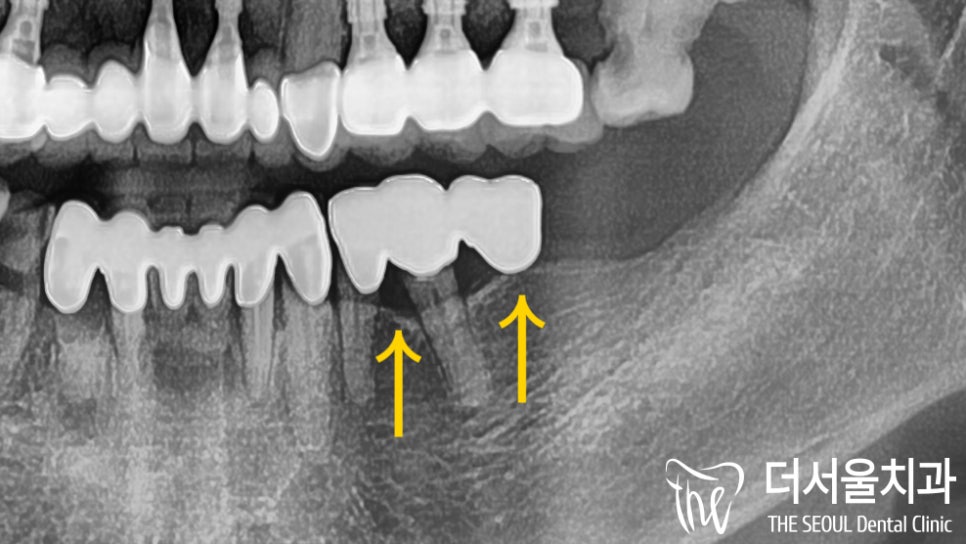

엑스레이 촬영을 통해 확인했는데요.

아.. 이미 염증이 생겨

치은 라인에 퍼져있네요.